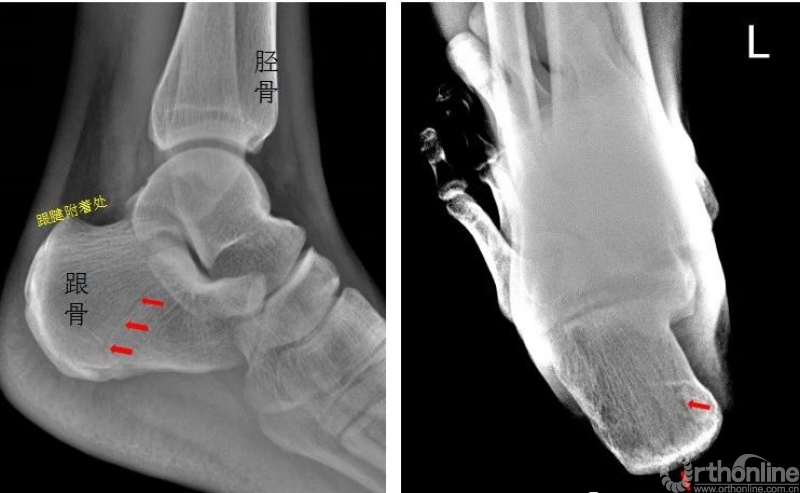

左侧跟骨见骨折透亮线,后缘骨皮质连续中断。左侧跟骨骨折

踝关节

右侧外踝骨皮质连续中断,可见透亮骨折线影,可见软组织稍肿胀影。右踝关节骨折

Warmreminder: 踝关节扭伤,许多大夫只做踝关节正侧位。有时踝关节正侧位不能看出有明显异常,而有局部软组织肿胀,活动受限时,根据我的经验,踝关节扭伤有时只做正侧位是有局限性的;小妙招足正位也是必不可少的。

此患者就是踝关节扭伤,踝关节正侧位未见异常,加拍足正位时发现外踝骨折。

所示右侧腓骨远端见斜行骨折线,骨折端对位对线尚可。右腓骨远端骨折。